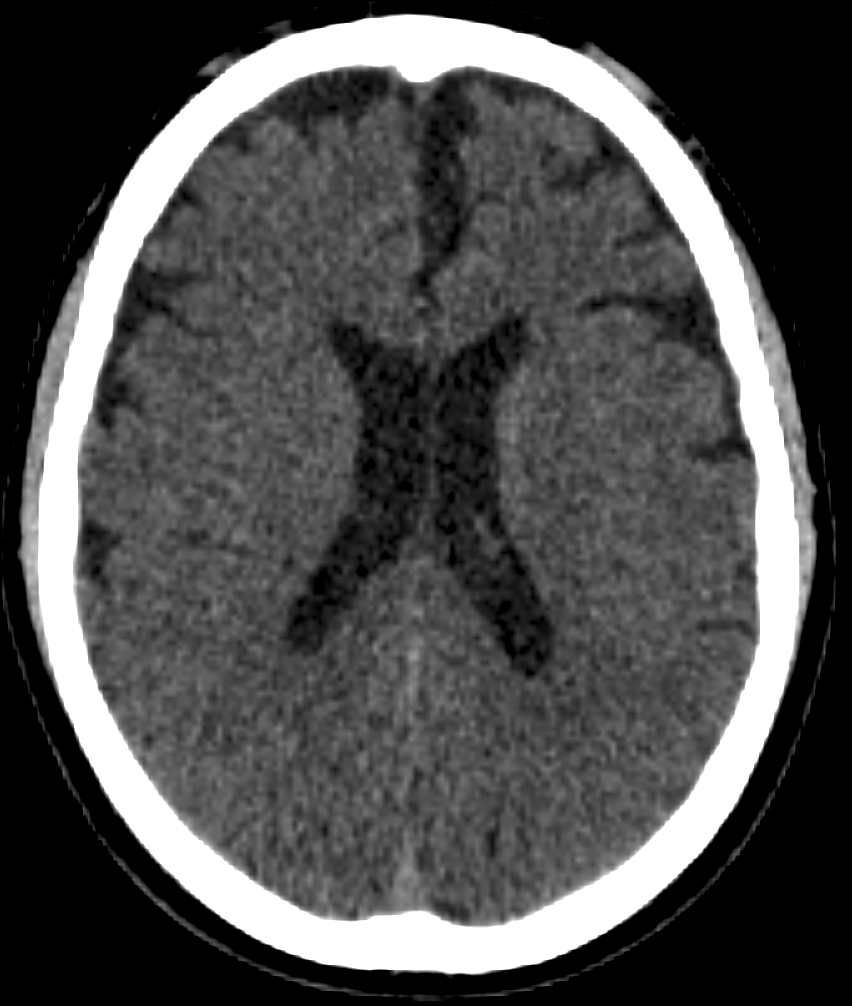

Refer to caption

(a) Inferior cervical slice (discarded).

(b) Skull base (discarded).

(c) Supratentorial brain slice (retained).

Figure 1: Illustration of the slice selection strategy used in this study.

By discarding the inferior and extreme superior portions of the head, the resulting dataset focuses exclusively on supratentorial brain anatomy, which is most relevant for ischemic stroke analysis and downstream modeling tasks. This selection also reduces anatomical variability unrelated to cerebral tissue organization, facilitating more stable and consistent learning of structural patterns by the generative model.